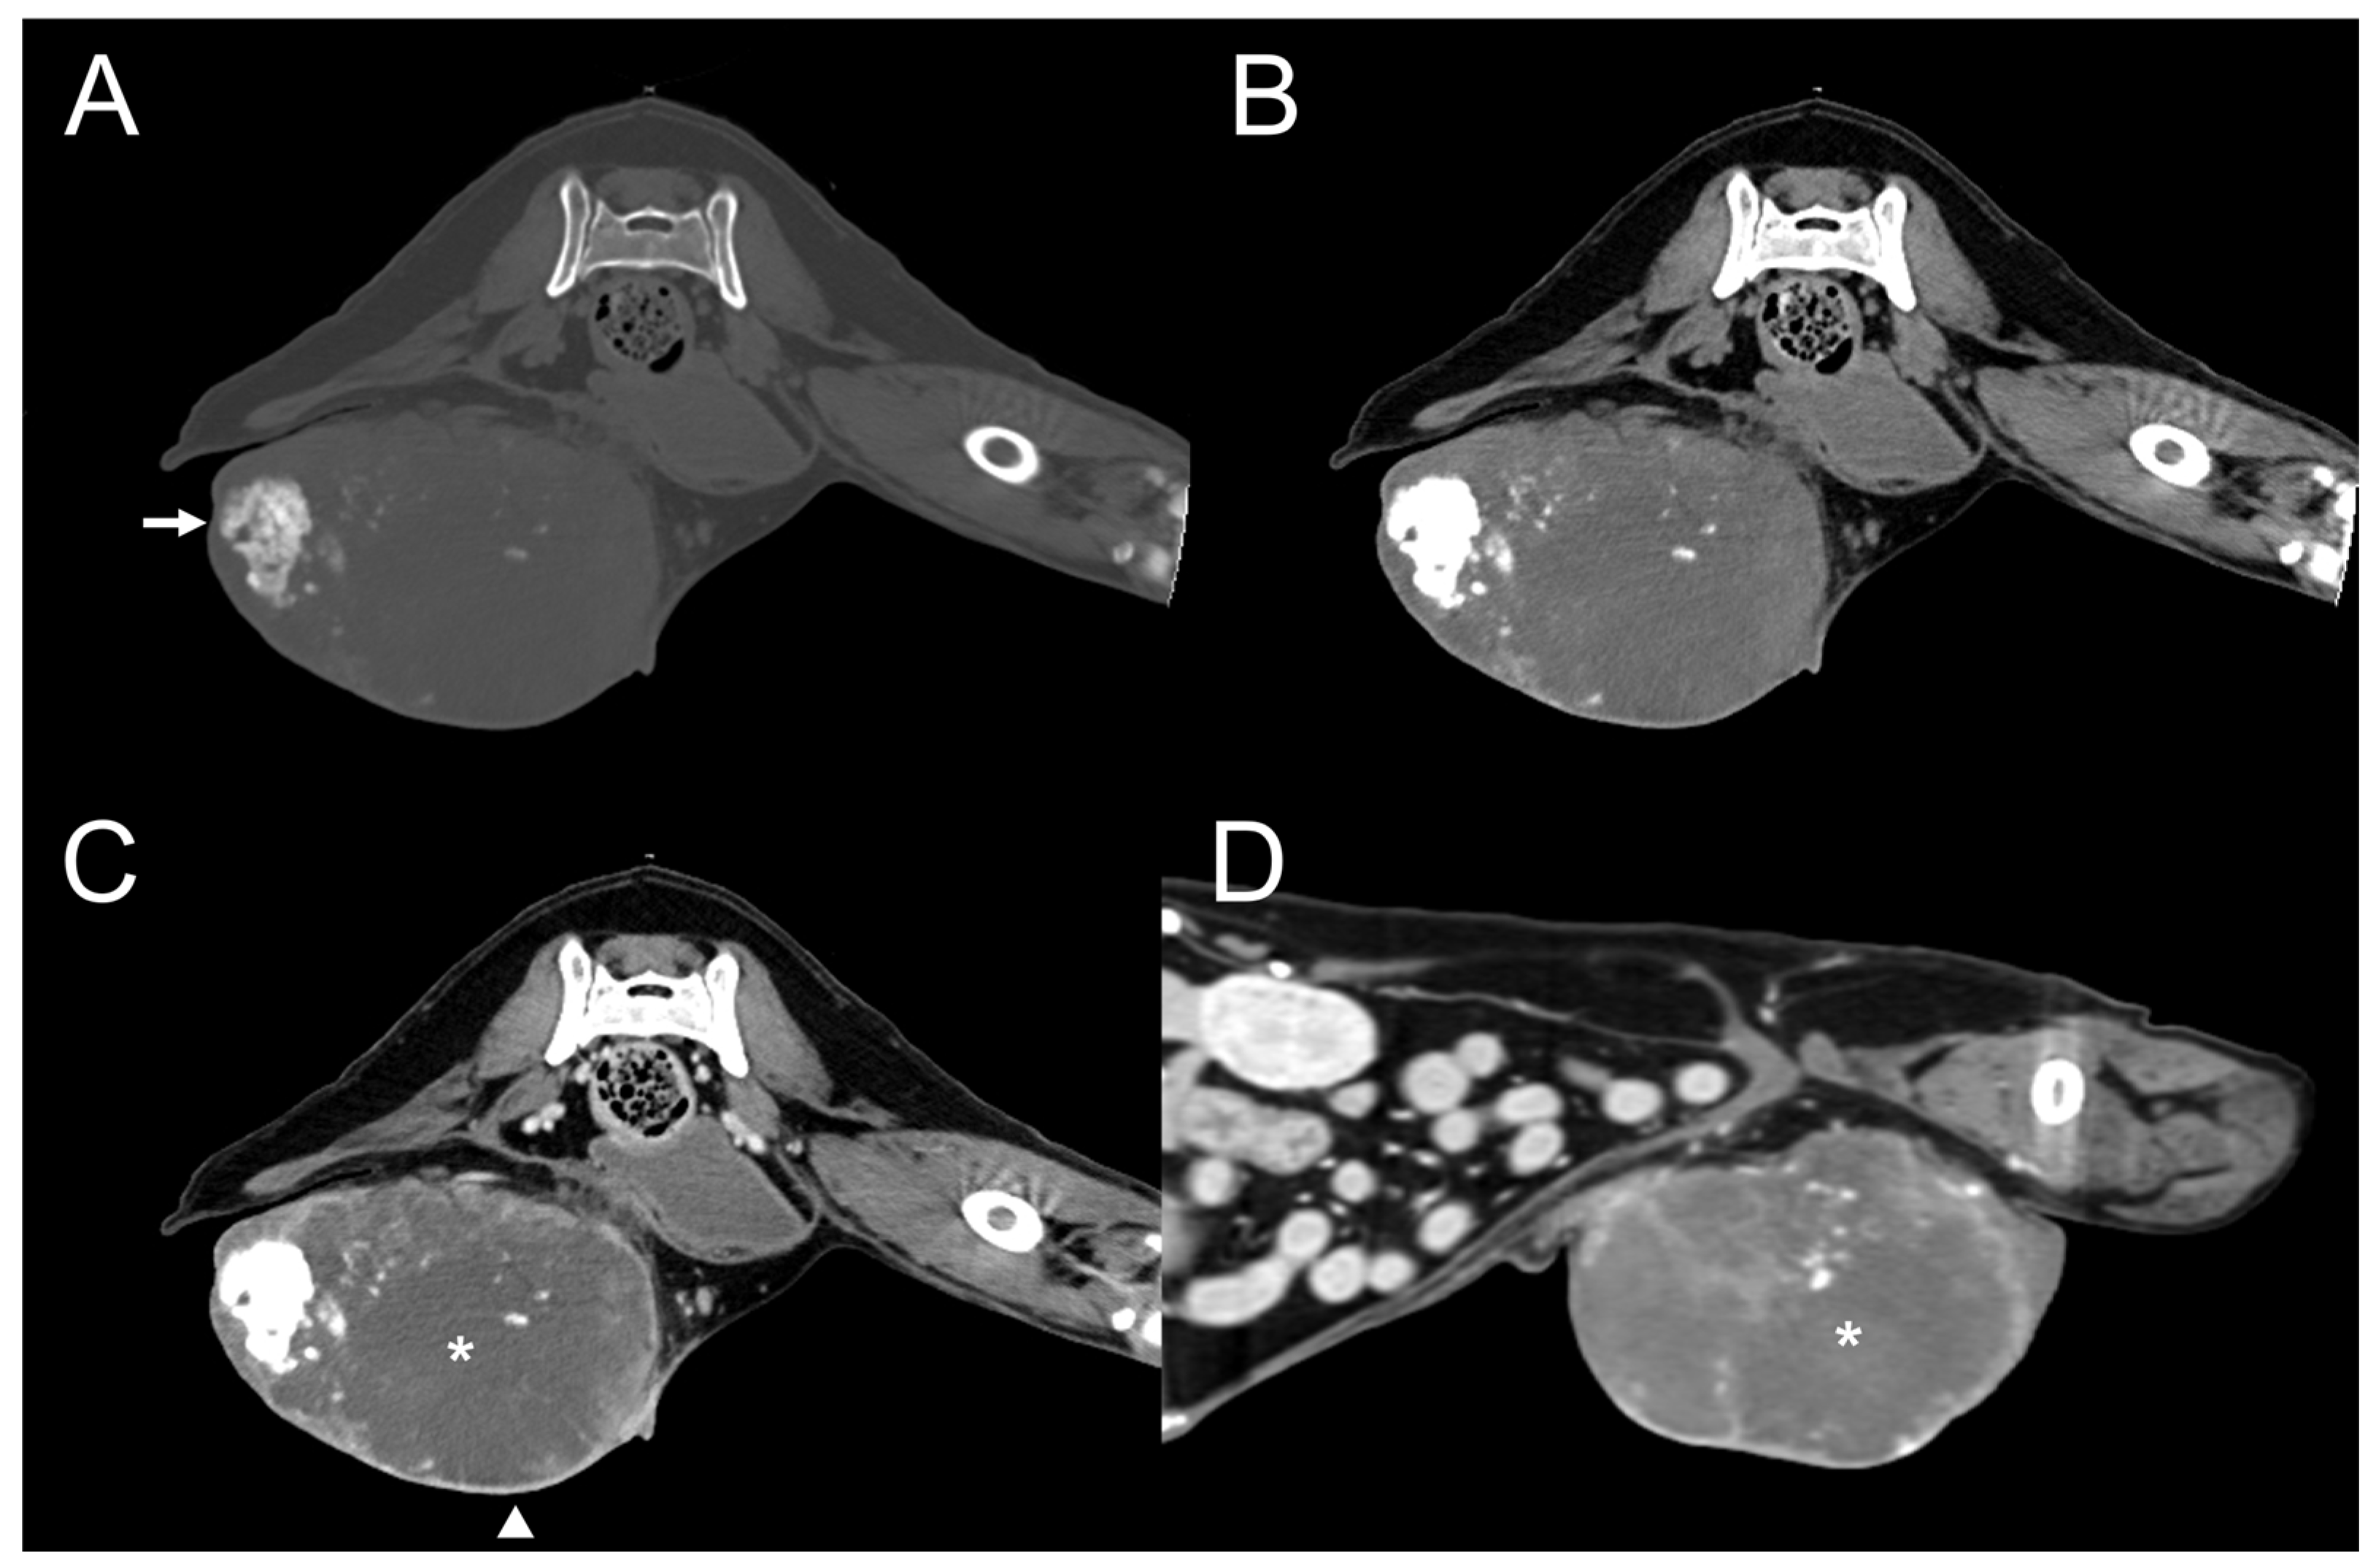

| Dog 5 | Mammary (rt. caudal) | Well-defined | Heterogenous | Present | Present | Moderate | Amorphous | Eccentric |

| Dog 6 | Small intestine | Well-defined | Homogenous | Absent | Present | Mild | Dot | Eccentric |